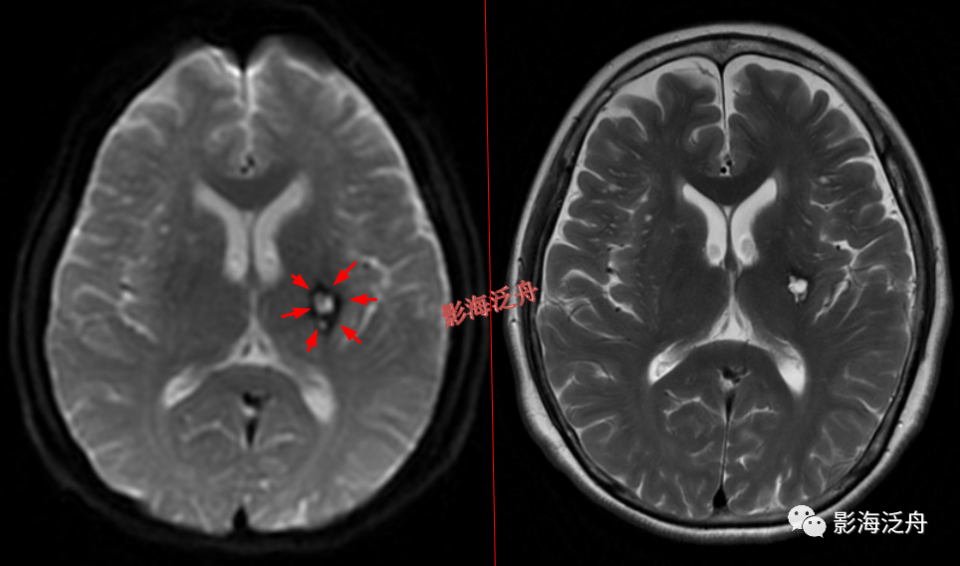

诊断腔梗灶的时候要注意与小的陈旧性出血灶相鉴别,如上图,T2WI序列上左侧基底节区可见不规则小片状T2WI高信号影,不仔细看很容易就诊断腔梗灶了,但在低b值DWI序列上病灶周围可见环状低信号影(红箭),代表含铁血黄素沉积,为慢性出血的特征性表现。